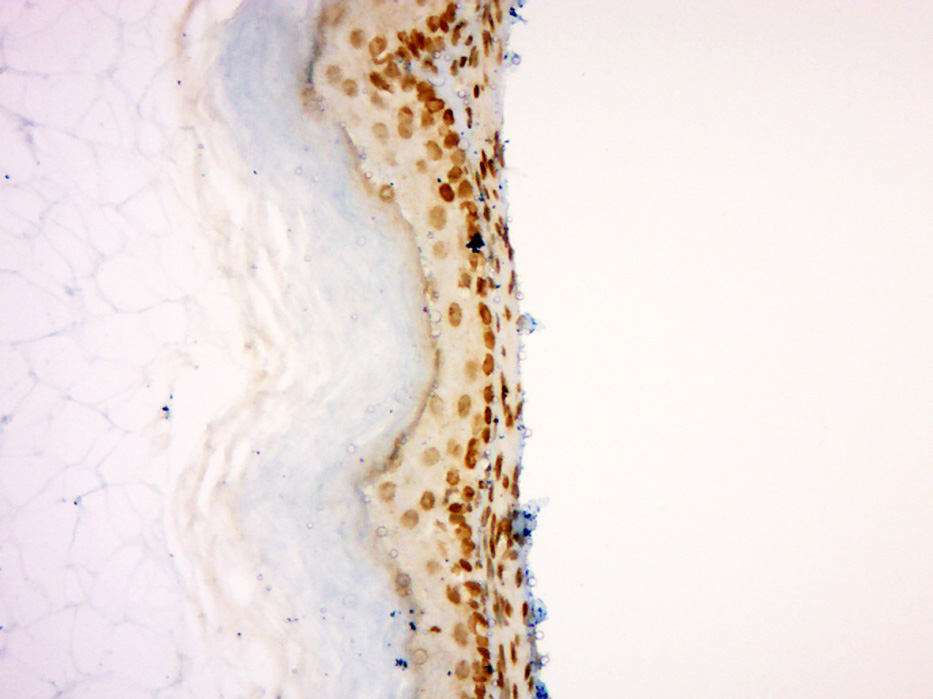

| 英文名称 | Dnmt3b Rabbit pAb |

| 中文名称 | DNA甲基转移酶-3β抗体 |

| 产品应用 | IHC-P=1:100-500, IHC-F=1:100-500, IF=1:100-500 Not yet tested in other applications. |

| {IHC-P} | {1:100-500} |

| {IHC-F} | {1:100-500} |

| {IF} | {1:100-500} |